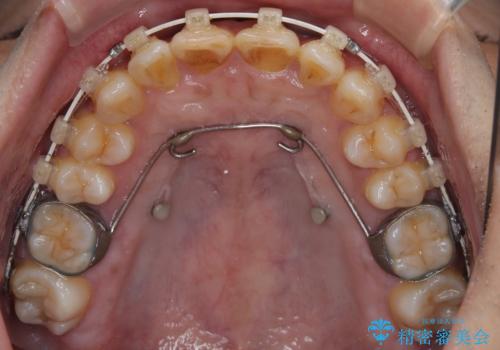

骨格性のディープバイト 補助装置を併用したワイヤー矯正治療で咬み合わせを改善

骨格的に上顎骨がやや前方にあり、それが原因で下顎前歯が隠れるほどのディープバイトになっている状態でした。

補助装置を用いて、上顎大臼歯を積極的に後方移動させながら、ディープバイトを改善していくこととしました。

強い咬合力に抵抗するため、上下ともに表側のワイヤー装置にて矯正治療を行うこととしました。